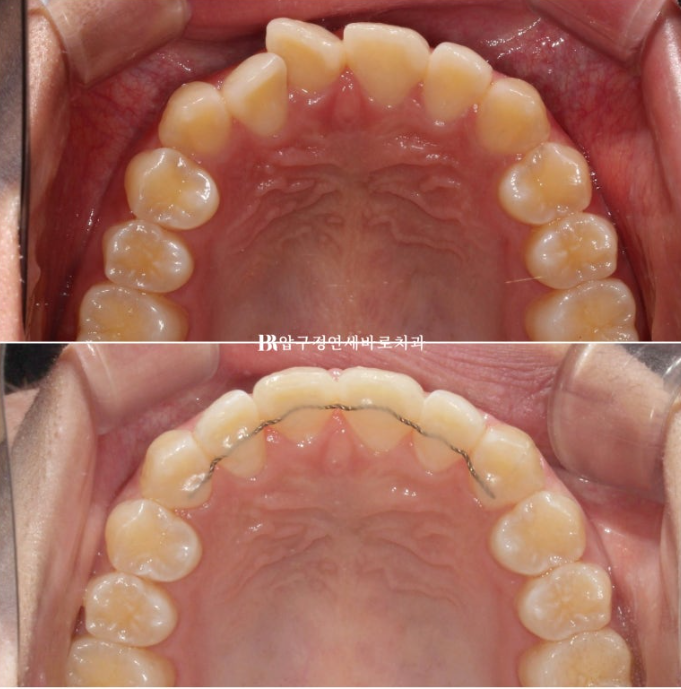

그리고 한달 후 24년 6월 드디어 치료를 마무리 했습니다.

24.06

배열은 가지런해졌고 앞니 교합도 처음에 비하여 깊어졌습니다.

유지장치까지 붙은 모습입니다.

전 후 비교 보겠습니다.

토탈 치료 기간은 6개월 입니다.

23.12~24.06